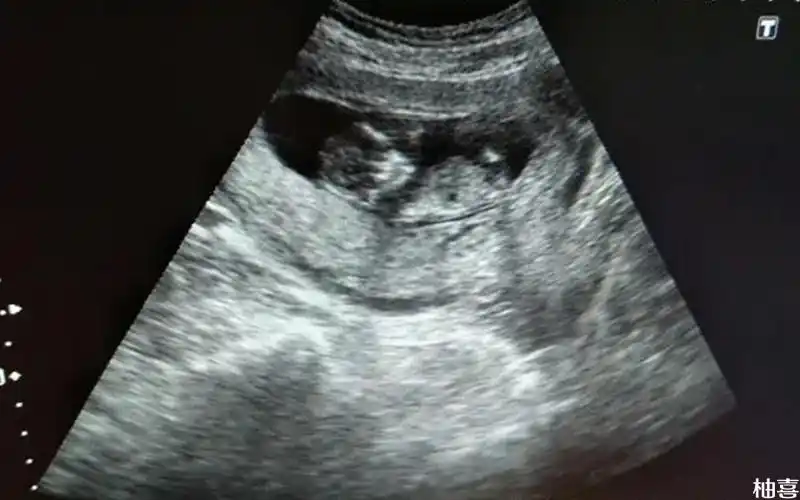

胎儿头臀长约5 9cm 大概怀孕多久?有12周左右吗

(一)胎儿头臀径的测量

头臀长正常值与孕周关系表

孕6周到14周胎儿头臀长参考值